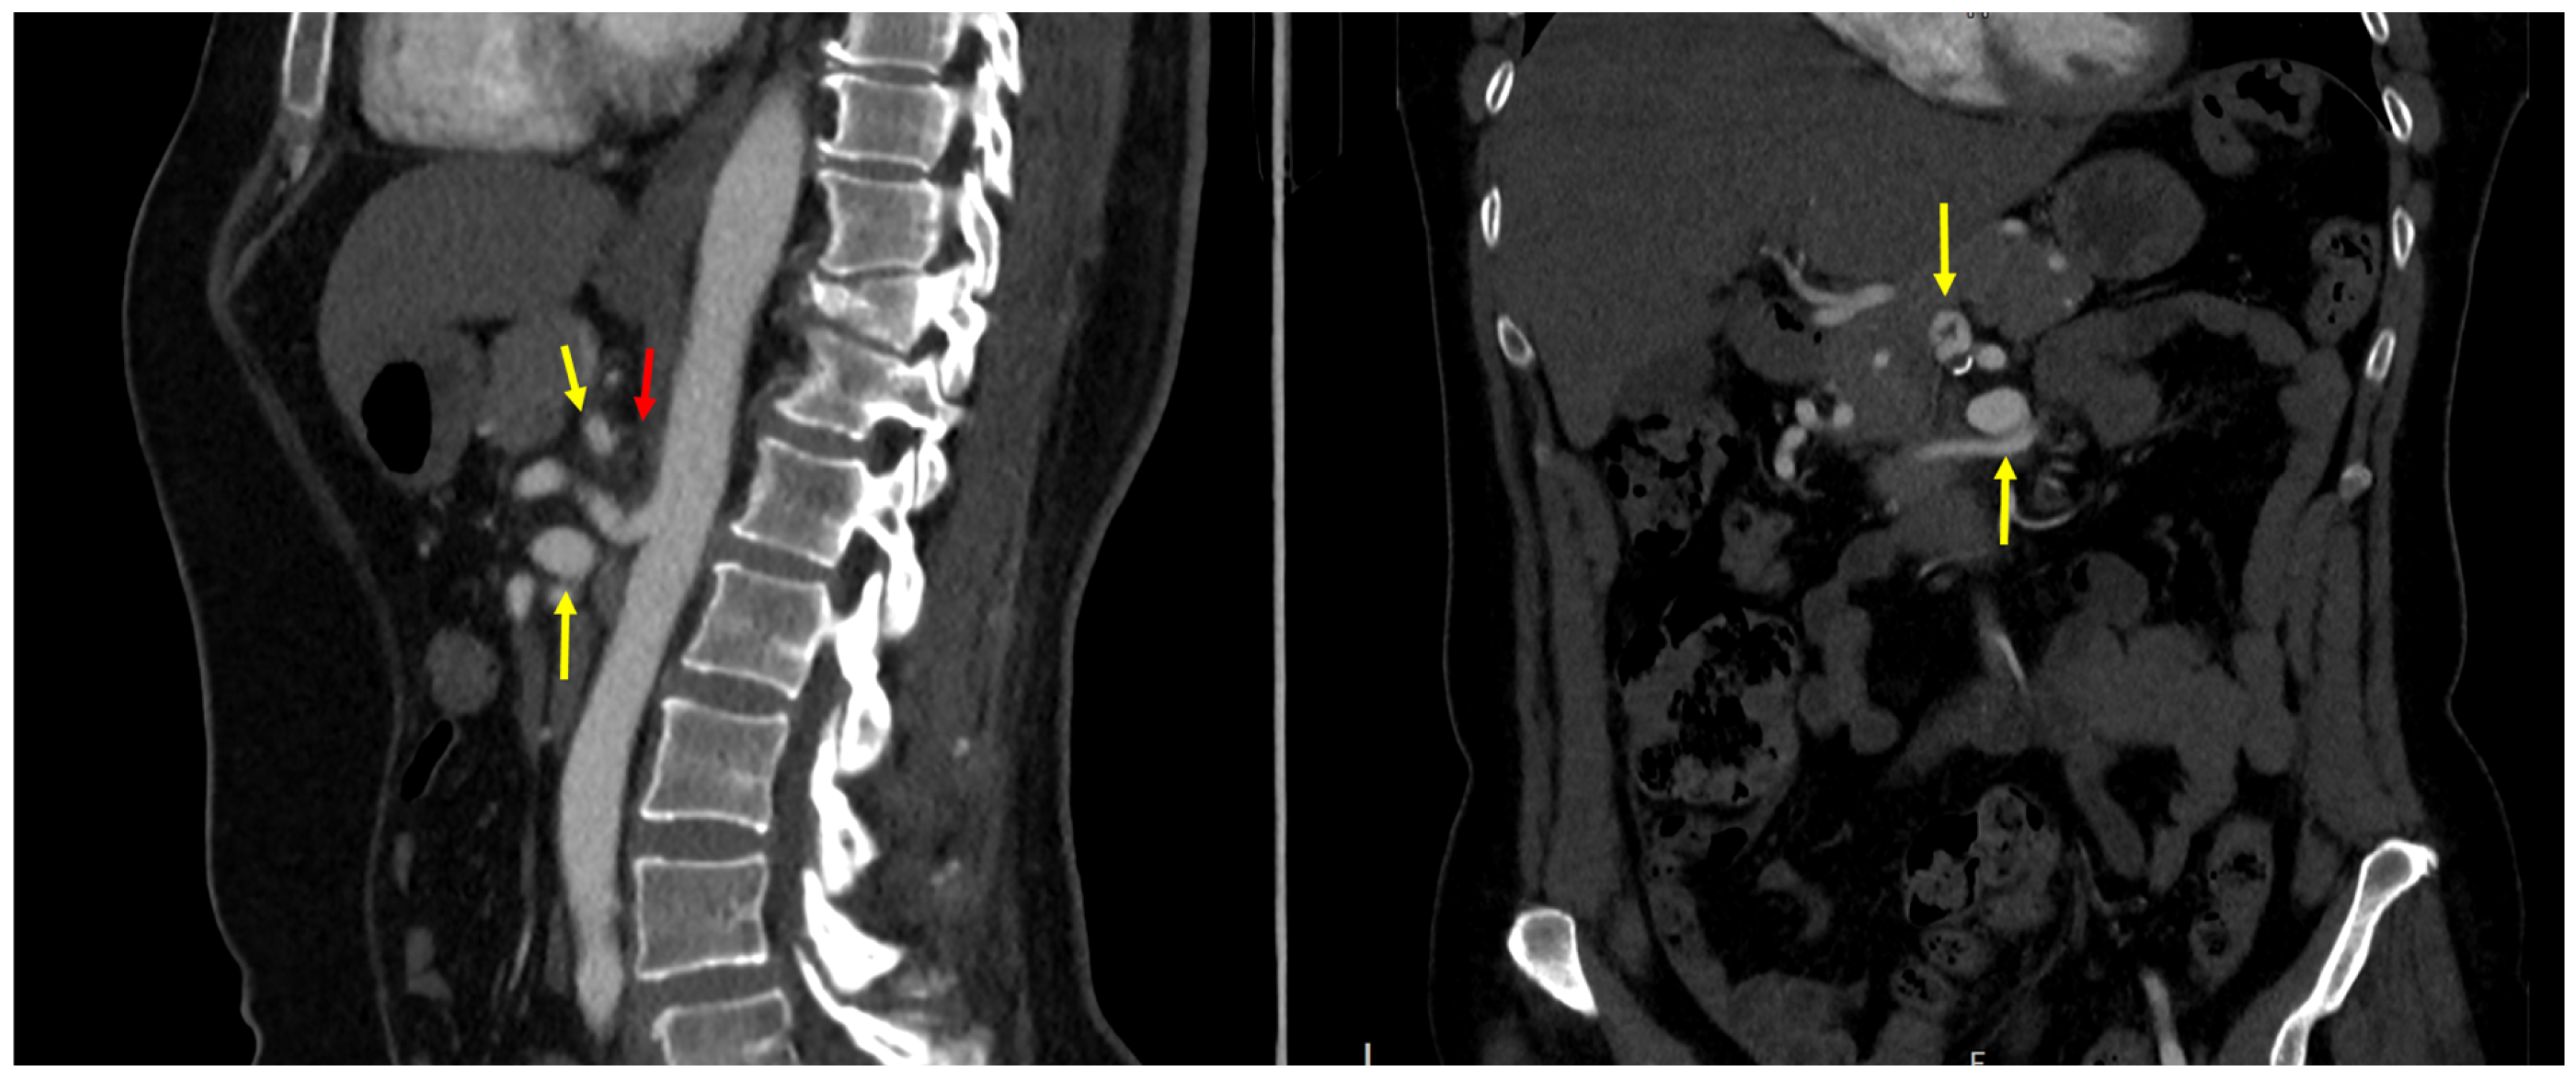

3.2. Anatomic Features and New Classification